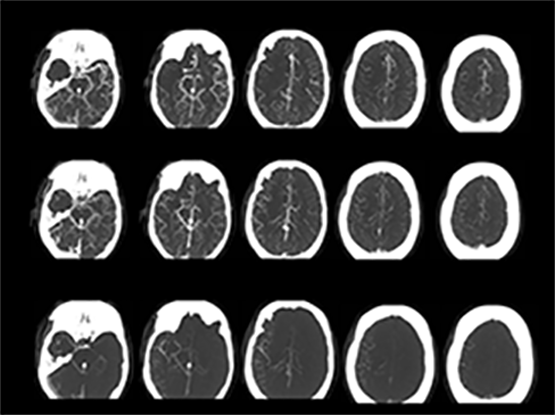

The clinical trial, known as ESCAPE (Endovascular treatment for Small Core and Anterior circulation Proximal occlusion with Emphasis on minimizing CT to recanalization times), shows there is a marked reduction in both disability and death among patients who receive ET for acute ischemic stroke. Ischemic stroke is caused by a sudden blockage of an artery to the brain that deprives the brain of critical nutrients, such as glucose and oxygen. Currently, the international standard of care based on Canadian, U.S. and European guidelines is to administer a drug called tPA when appropriate. Known as a ‘clot buster’, the drug dissolves the blood clot.

ET is performed by inserting a thin tube into the artery in the groin, through the body, and into the brain vessels to the clot. This is done under image-guided care using an X-ray. The clot is then removed by a retrievable stent and pulled out, restoring blood flow to the brain.

Endovascular treatments were first developed in the 1990s, but ET has only recently been technically possible. The ESCAPE team says the success of the trial can be credited to very fast treatment and the use of brain and blood vessel imaging. In ESCAPE, researchers were on average two hours faster in opening the blocked blood vessels than in previously reported trials.